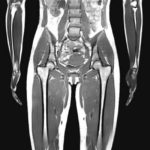

MRI写真で見ると衝撃!女性のダイエット・ビフォーアフター

自分のどこに余分な皮下脂肪がついているか想像できるだろうか。その想像をキープして、このMRI写真を見て欲しい。あなたの想像を打ち砕くに違いない、衝撃にあふれたビフォーアフター写真である。